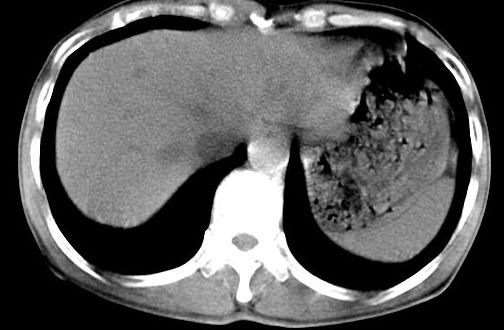

病人资料:男,50岁,上腹部隐痛,消瘦乏力,有乙肝病史二十余年,b超提示肝内内占位。

由于是基层医院,机器速度跟不上,增强效果差,请各位老师也看看!

肝右叶后下内侧段占位:肝癌可能性大

肝内占位,考虑肝局灶性结节增生,不除外肝癌.胰尾好象有占位?

增强动脉期应该没有捉到,可能病灶强化密度已下降了,支持考虑肝癌

肝右叶后段低密度灶,增强受机器限制,特点不明显,无等密度充填及周围强化,结合病人乙肝史20年,首先考虑肝癌。

肝右后叶占位,增强时期没抓好,特点不明显,结合病史首先考虑原发性肝癌